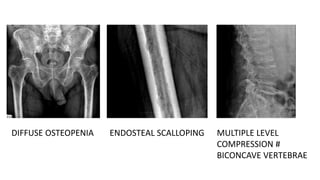

• XRAY

• Multiple punched out sharply demarcated lytic lesions without surrounding

reactive sclerosis.

• Diffuse osteopenia

• Occasionally bone expansion is seen- Ballooned appearance

• Spine – Osteoporosis & VB collapse

Multiple level compression # and Biconcave Vertebrae

DIFFUSE OSTEOPENIA ENDOSTEAL SCALLOPING MULTIPLE LEVEL

COMPRESSION #

BICONCAVE VERTEBRAE